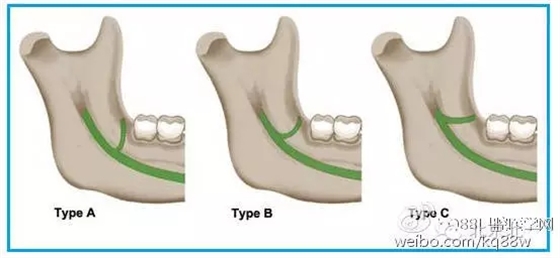

磨牙后三角(retromolar triangle,RMT)是位于下頜最后磨牙后方一處凹陷區(qū)域。磨牙后三角在口腔外科臨床工作中是一處非常重要的區(qū)域,下頜第三磨牙的有無以及牙槽骨的吸收造成其解剖形態(tài)及結(jié)構(gòu)多變。

640.webp.jpg

圖一 磨牙后區(qū)的形態(tài)學(xué)分類(綠色標(biāo)示):A.水滴形;B.細(xì)長型;C.三角形。